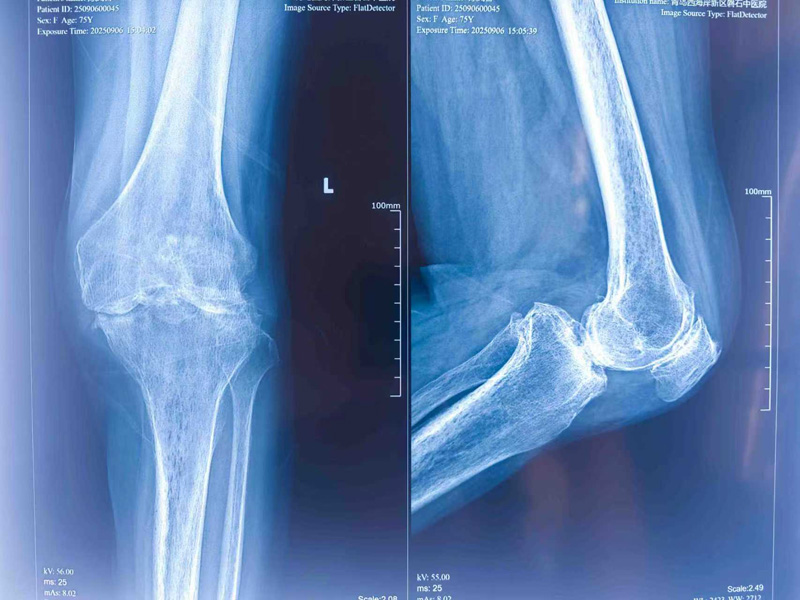

李连亭主任团队对患者的病情进行了全面、细致的评估,确诊其为重度膝关节骨性关节炎,关节软骨已严重磨损,保守治疗无效,进行全膝关节置换术是帮助其恢复行走功能的唯一有效途径。面对我院首例此类手术,团队高度重视,组织了多次术前讨论,为患者量身定制了周密的手术方案和应急预案,确保万无一失。